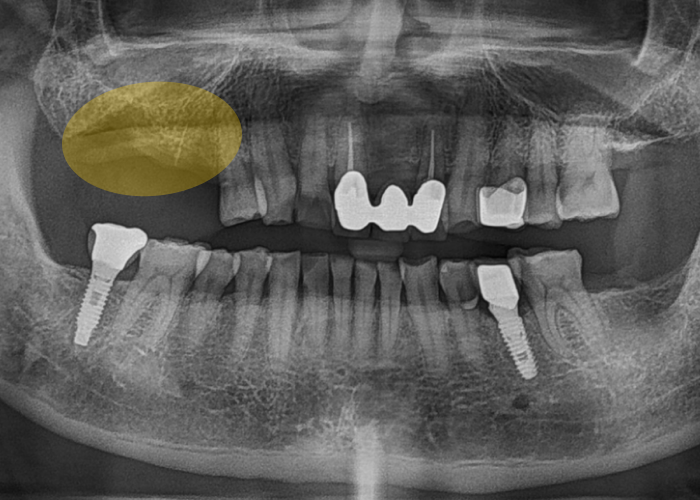

식립이 끝난 뒤에는 뚜껑을 씌워

잇몸이 차분히 회복될 수 있는 환경을

만들어줍니다.

이 잇몸이 단단히 자리 잡는 데에는

보통 약 4개월 정도의 시간이 필요합니다.

그 기간 동안 환자분께서는

당일에 제작된 임시 치아를 사용하시면서

일상생활을 이어가실 수 있습니다.

즉,

치료 중에도 식사나 대화에

큰 불편 없이 생활하실 수 있도록

배려한 과정이라 보시면 됩니다.